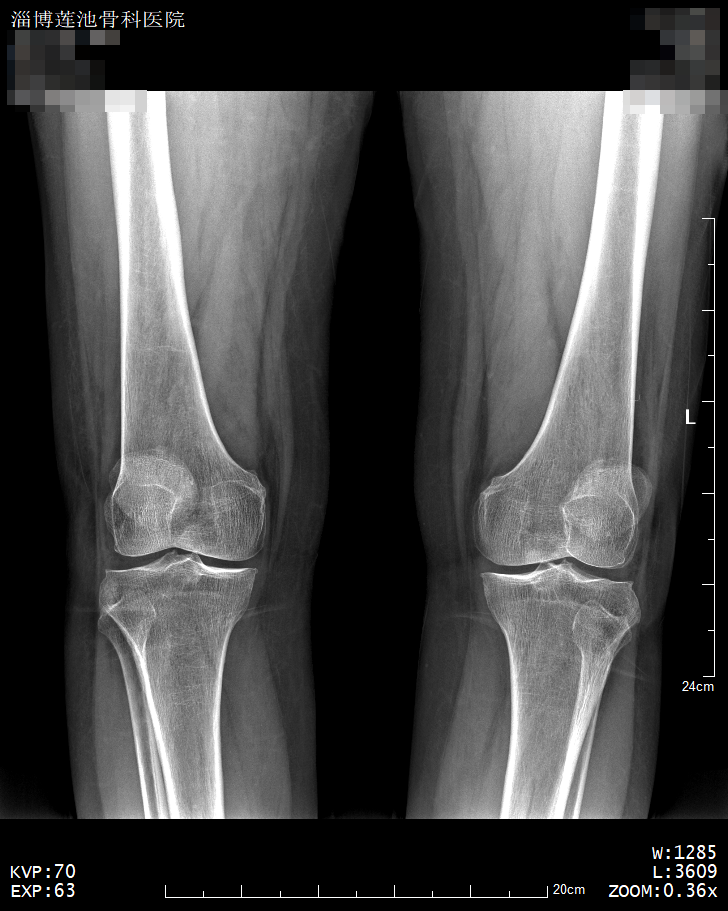

X线检查是传统的影像学检查手段,检查费用低,适合多数患者常规检查,尤其是疾病初筛的首选检查方式。对于骨折移位、有骨质改变的骨病、关节部位骨性病变、不透光异物存留、心肺器质性疾病、消化系统梗阻等疾病有很好的诊断价值。

缺点:受制于深浅组织的影像相互重叠和隐藏,有时需要多次多角度拍摄X光片才能看清。 ‍